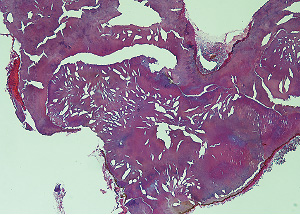

を抜歯後、周囲の肉芽様組織の掻爬を行った。大小さまざまな複数の茶褐色の硬固物が歯根に付着していた(図❸❹)。抜歯窩骨面は正常で、上顎洞への交通なども認めなかった。摘出物は、病理組織検査に提出し、炎症性肉芽組織および歯石との診断を得た(図❺)。

図❺ 病理組織写真(×100)